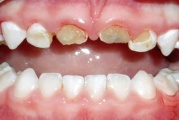

Fluoroos

Fluoroosi

Hammaste defektid